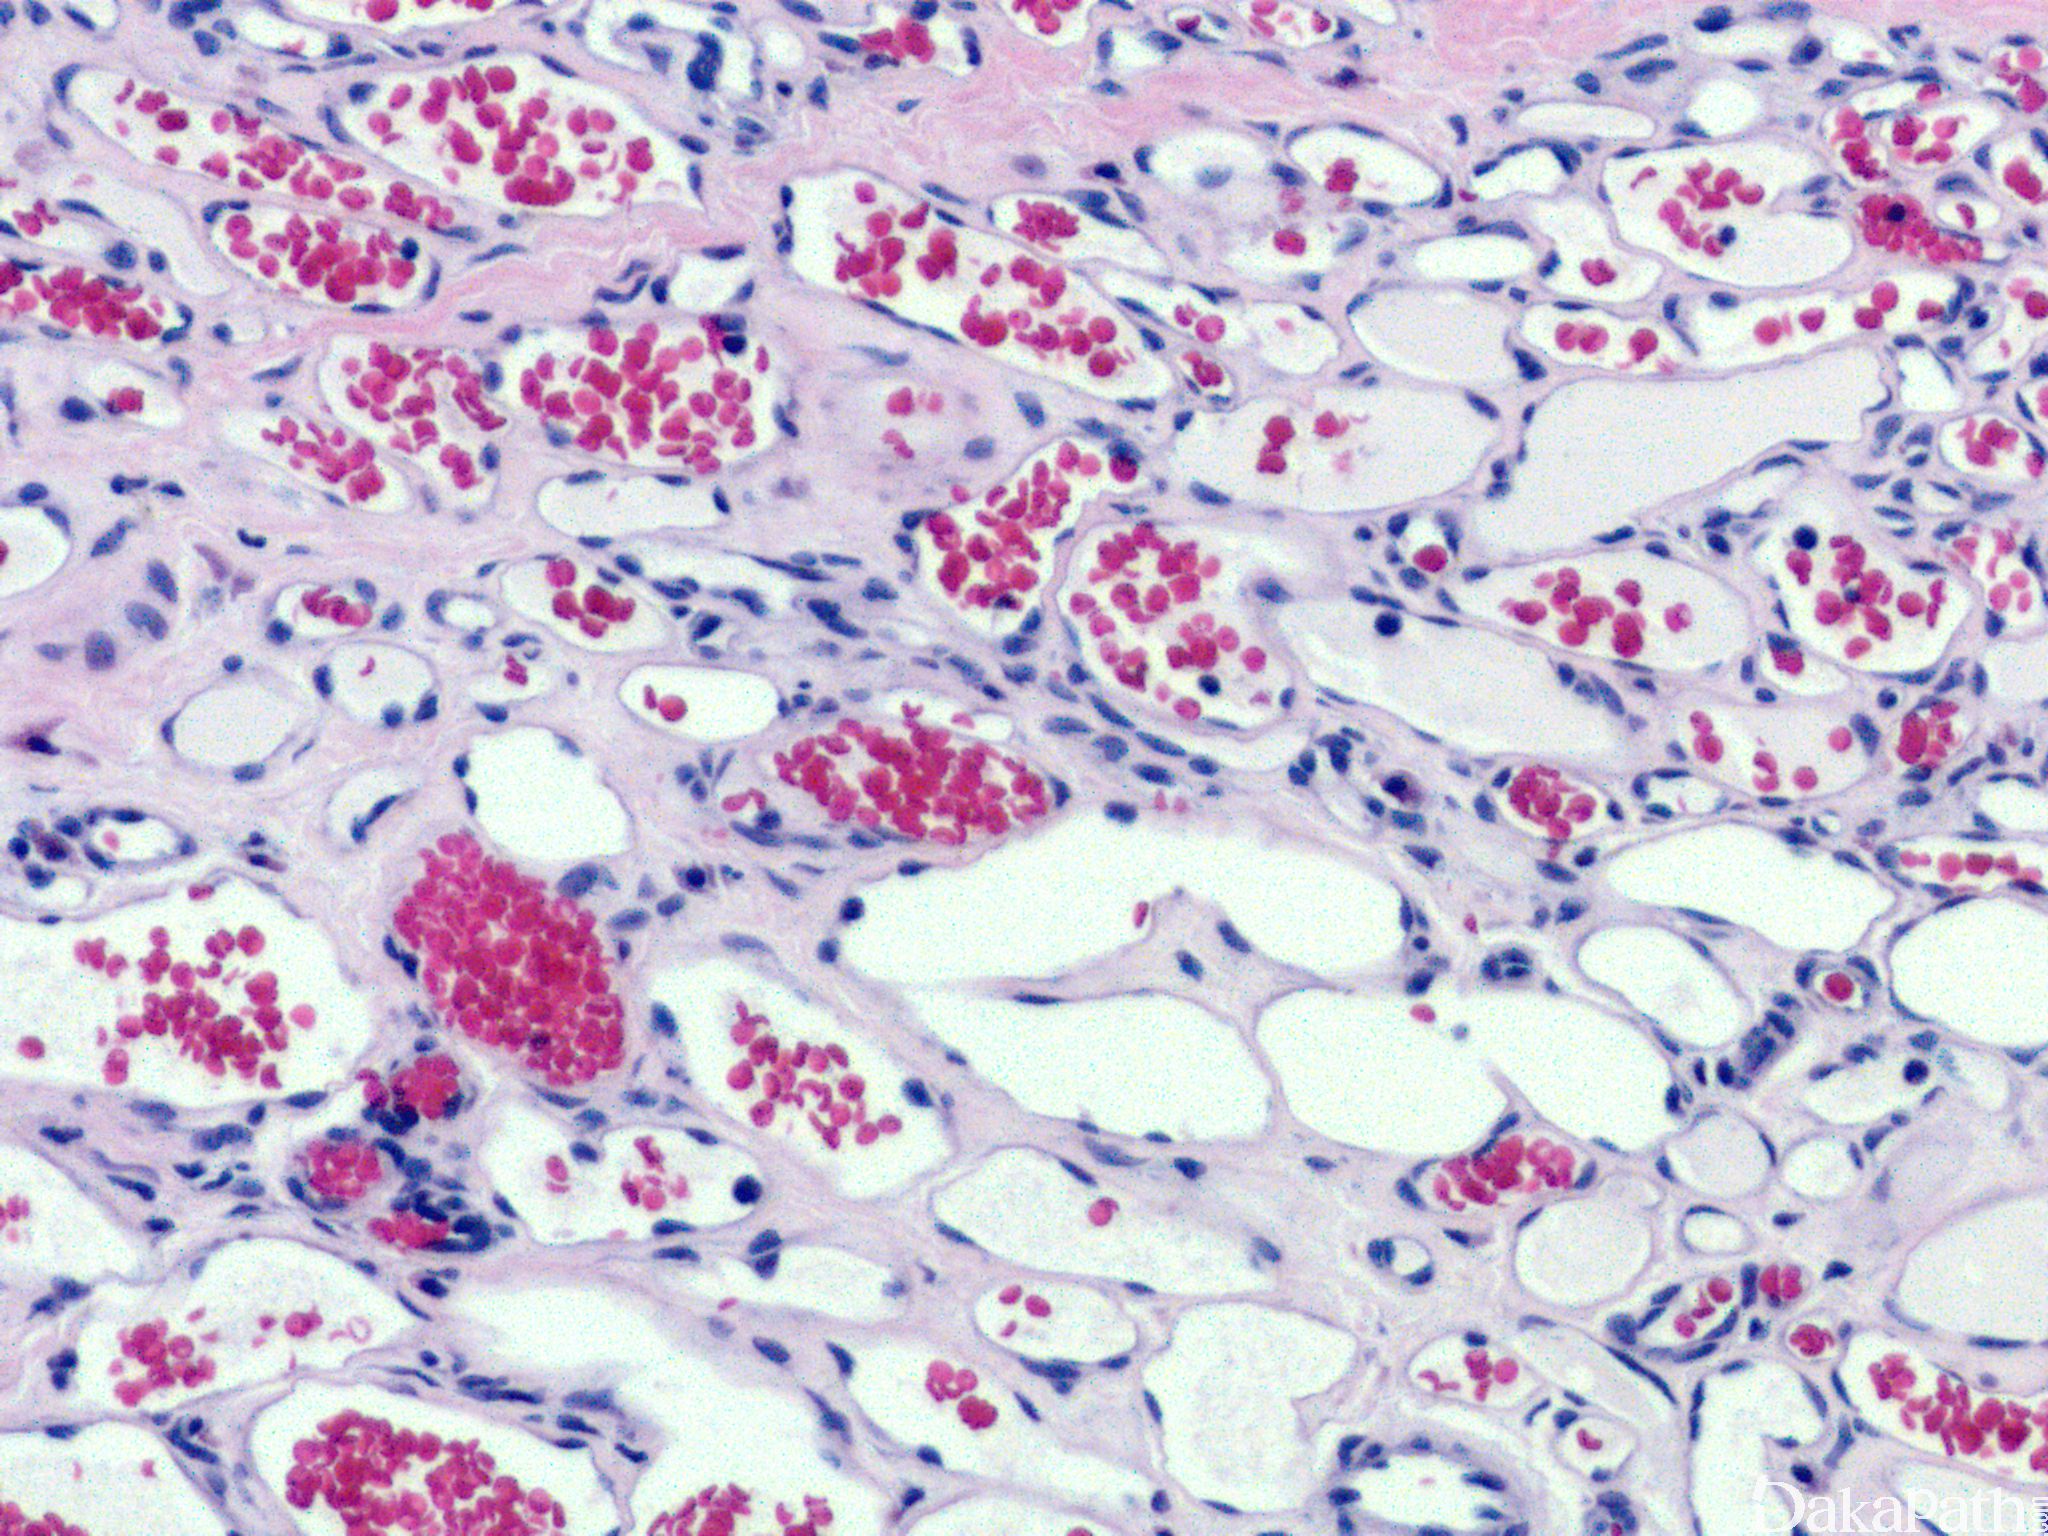

化脓性肉芽肿(分叶状毛细血管瘤)

pyogenic granuloma